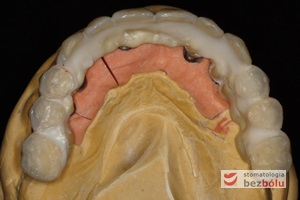

Gotowa praca protetyczna - korony cerkonowo-ceramiczne na modelu roboczym dostarczone z laboratorium protetycznego

Gotowa praca protetyczna – korony cerkonowo-ceramiczne na modelu roboczym dostarczone z laboratorium protetycznego